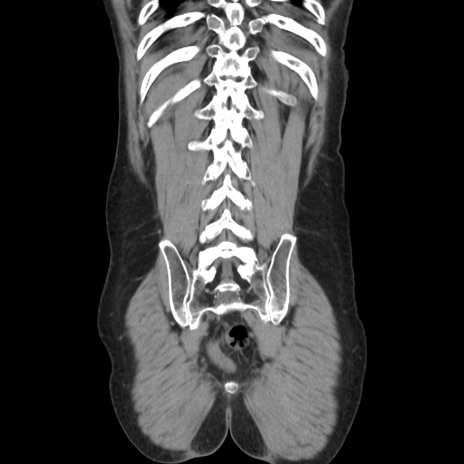

症例37(冠状断像)

【症例】40歳代 男性

【主訴】腹痛

【現病歴】4時間ほど前に電車に乗車中に臍部上より腹痛出現。徐々に増悪し起立困難となり、救急外来受診。生ものは数日食べていない。今朝お雑煮を食べた。

【身体所見】BT 36.8℃、BP 117/84mmHg、HR 91/min、SpO2 97%、苦悶様、腹部:臍上部広範囲圧痛あり、反跳痛±

【データ】WBC 8100、CRP 0.03